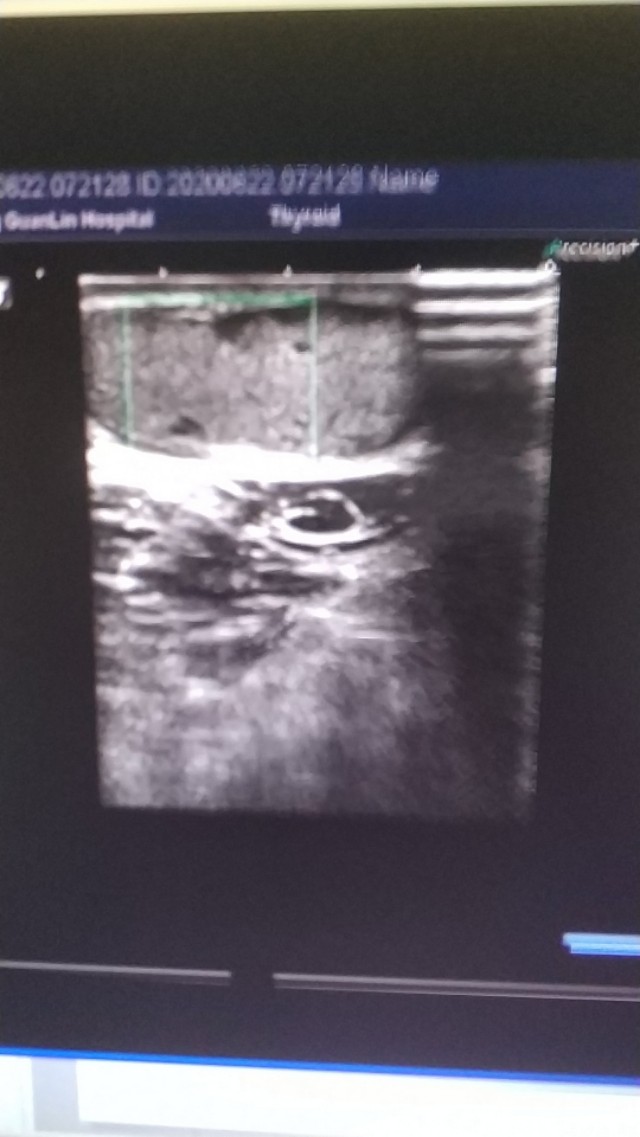

上图是一个左膝部的表皮囊肿,与皮肤真皮层关系密切,里面回声细密伴裂隙样低回声。